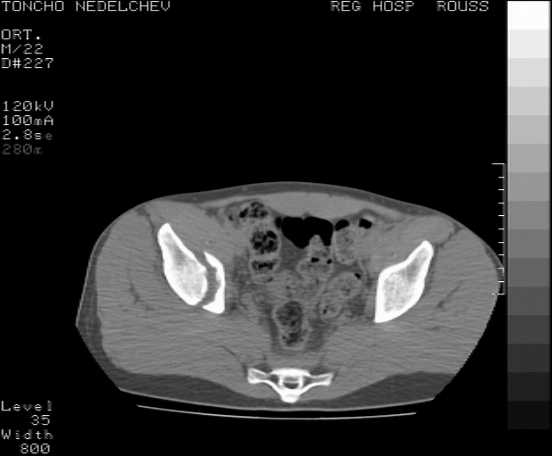

Re: Acetabular fracture

Here are some more axial images. What is your opinion as for the timing of the operative treatment?